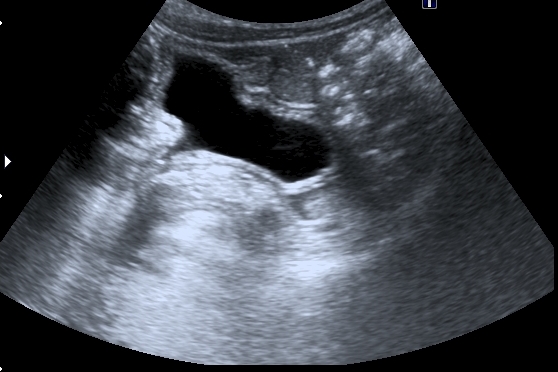

Меня больше всего заинтересовало тканевое образование в нижнем полюсе левой почки - гиперэхогенное, многоузловое. Есть мысли про причину такого состояния почек, но пока хочу выслушать мнения коллег. Буду очень благодарен за отзывы.

Спленомегалии нет. печень без признаков фиброза . Почки уменьшены ( правая - 50 х 20 мм, левая - чуть больше , но за счёт образования нижнего полюса). В левой почке в образовании - есть одиночная небольшая киста ( см клип про почки №3), но на поликистоз непохоже. Ещё одно "но" : с аутосомно - рецессивной поликистозной болезнью почек до 10 лет не живут.

Ну и тумор слева.

"Маленькие белые почки" с расширением ЧЛС и мочеточников, умеренной латерализацией устьев, без видимых на высокочастотном УЗИ кист. Печень без видимых на высокочастотном УЗИ кист. Опухоль слева.

МЦУГ, перевод в Минск (нефректомия слева + трансплантация почки).